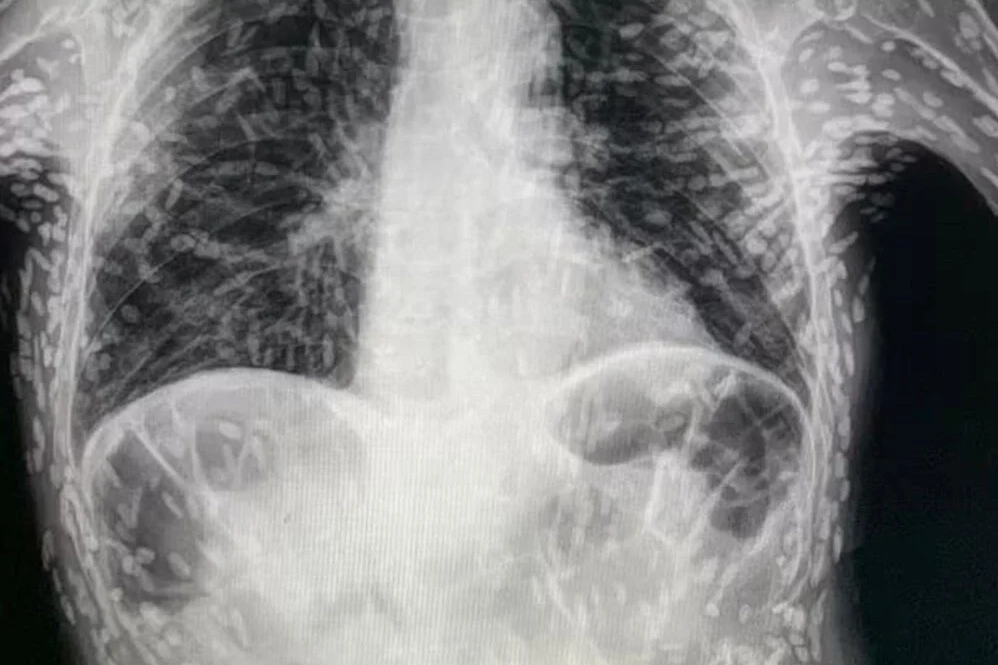

Bir doktorun Twitter'da paylaştığı röntgen, her biri bir parazitin yerleşmiş kalıntılarını temsil eden yüzlerce parlak lekeyi gösterdi.

Sistiserkoz olarak adlandırılan durum, normalde bağırsaklarda yaşayan bir tenya türünün larvalarının kas veya beyin gibi dokulara girmesiyle ortaya çıkıyor. İnsanlar, başta et ve yıkanmamış meyve ve sevze olmak üzere kontamine yiyecekleri kazara yutarak bu tenyalar ile enfekte oluyor. Larvalar, deriden hissedilebilen kistler şeklinde sert yumrular oluşturuyor.

Bununla birlikte, tenyalar hızla öldüğü için durum genellikle zararsız olarak kabul ediliyor. Ancak ölü tenyalar geride bıraktığı kistler ölüme varabilen sağlık sorunlarına neden olabiliyor. Kistler akciğerlerinize yapıştığında ise öksürük ve göğüs ağrısı oluşuyor.

Görüntüyü paylaşan Brezilya'daki Botucatu'daki Hospital das Clínicas'tan Dr. Vitor Borin de Souza, hastanın öksürük şikayetiyle geldiğini ve durumun MRI ile rontgen taramalarında anlaşıldığını söyledi.